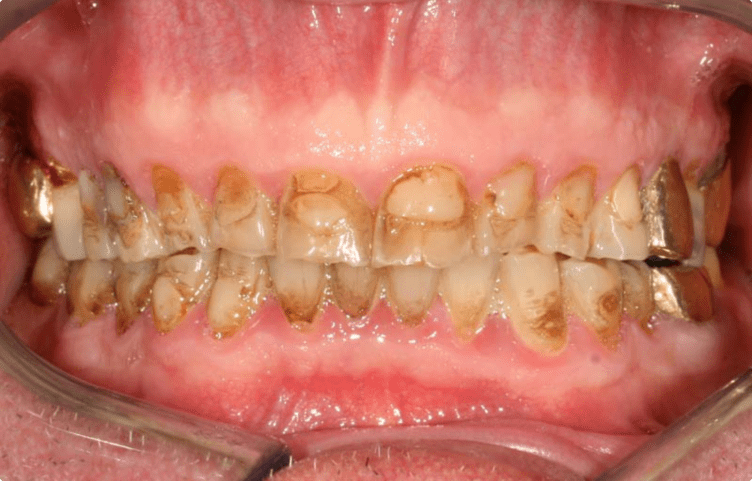

Ukázky zákroků

Podívejte se na konkrétní výsledky naší práce. Díky moderním postupům, preciznímu přístupu a zkušenému týmu dokážeme obnovit funkčnost i estetiku chrupu tak, aby výsledek odpovídal individuálním potřebám každého pacienta. Níže najdete reálné případy našich klientů – srovnání před a po.

MDDr. Petr Caha